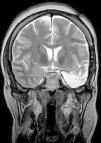

Para ello presentamos dos casos de pacientes mujeres de 50 y 42 años con crisis desde la infancia y diagnosticadas de esclerosis temporal mesial. Ambas fueron intervenidas por nosotros en el año 2000 mediante amigdalohipocampectomía con resección parcial amigdalar más lobectomía temporal izquierda y derecha respectivamente. Las dos pacientes no presentaron nuevas crisis parciales complejas durante los primeros 6 años, empeorando posteriormente por lo que fueron reintervenidas para monitorización con electrodos subdurales y profundos. En ambas se evidenció un inicio ictal compatible con el electrodo situado en la amígdala. La subsiguiente resección del tejido donde se situó el electrodo amigdalar dejó a las dos pacientes libres de crisis.

En estas dos pacientes fue preciso completar la resección amigdalar para conseguir que quedaran libres de crisis. La resección amigdalar es parte importante de la técnica quirúrgica en la epilepsia temporal mesial. Es posible que la amígdala tenga un papel mucho más relevante de lo actualmente considerado en el origen de las crisis.

Two patients are presented who were 50 and 42 years old at the time of surgery. They suffered from seizures since childhood and were diagnosed with mesial temporal sclerosis. A temporal lobectomy with hippocampectomy and partial amygdalectomy was performed on both patients in the year 2000, with one patient operated on the right side and the other one on the left side. Both patients were seizure free after surgery for 6 years, but presented again with seizures after that time. They were evaluated again for surgery, and subdural grids were placed, together with a deep electrode in the remnants of the amygdala. The amygdalar electrode showed to be the seizure onset in the two cases, and its resection rendered both patients seizure free.

These two patients show that a complete amygdalar resection is necessary to render some patients seizure free. It might be the amygdala has a greater role than previously thought.